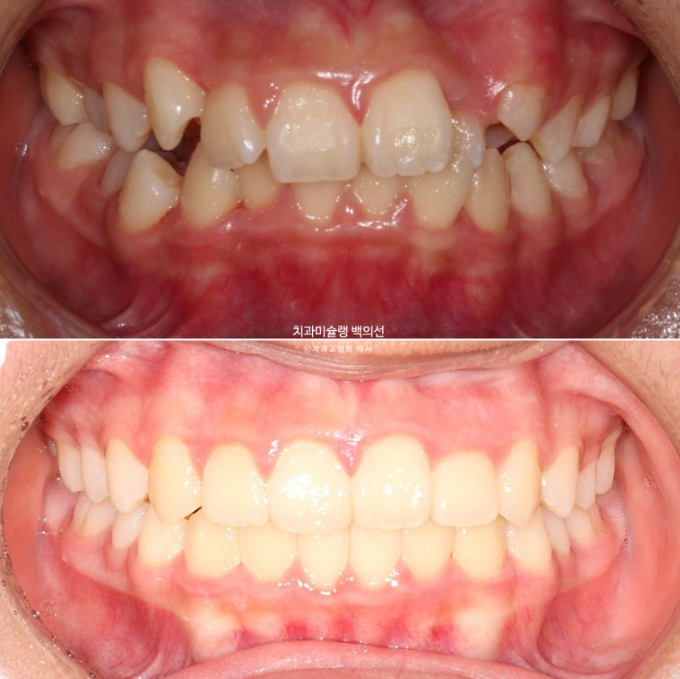

이제 전후비교 보겠습니다.

24.02~25.07

어긋난 중심선이 맞아졌으며 기울어진 앞니 치축도 좋아졌습니다.

앞니가 깊게 물리는 과개교합도 좋아졌습니다.